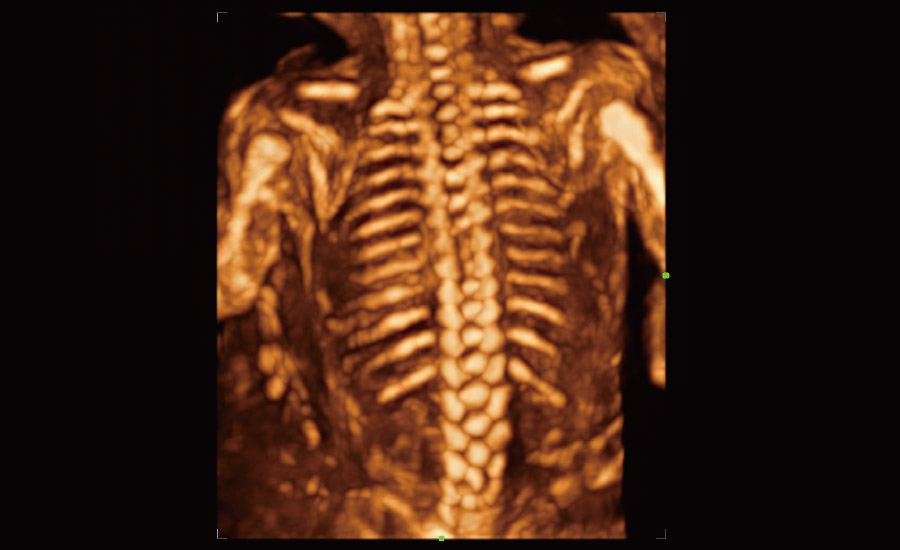

UMA (Ultra-Micro Angiography)

The innovative technology breaks the bottlenecks of traditional Doppler imaging. With ultra-high spatial resolution and flow sensitivity, it allows detecting super-subtle and super-slow flow perfusions, thereby extending the clinical application of qualitative and quantitative ultrasound evaluation in fetal brain, kidney, placenta, endometrium, ovary, etc.

UMA - fetus renal flow

3D UMA - fetus intracranial flow